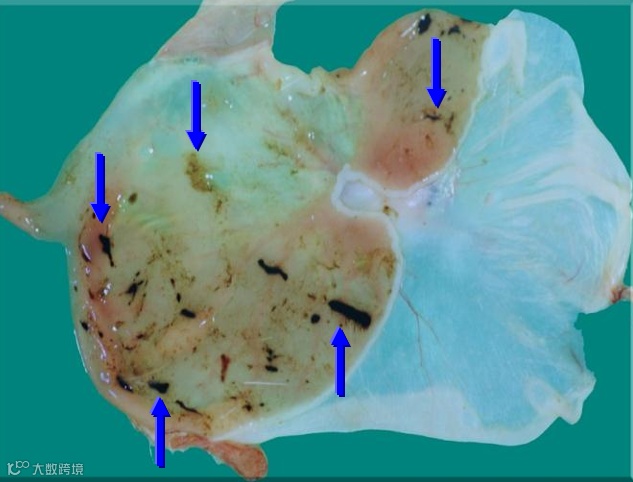

糜烂指粘膜浅表(不影响粘肌层)的局部坏死,出血及脱落等;溃疡指粘膜整层(包括粘膜肌层)的局部坏死,出血及脱落等。如下图所示。

大鼠腺胃–糜烂与溃疡

大鼠腺胃–糜烂